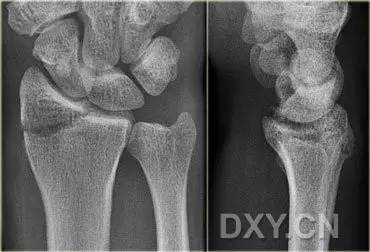

6. Bennett 骨折

第 1 掌骨基底的斜形骨折,掌骨近端形成轴向移位,掌侧边缘形成三角形的骨碎片。

(来源:Radiopaedia)

10. Rolando 骨折

第一掌骨基底的 T 或 Y 型粉碎性骨折,可伴有关节半脱位。

(来源:AO foundation)